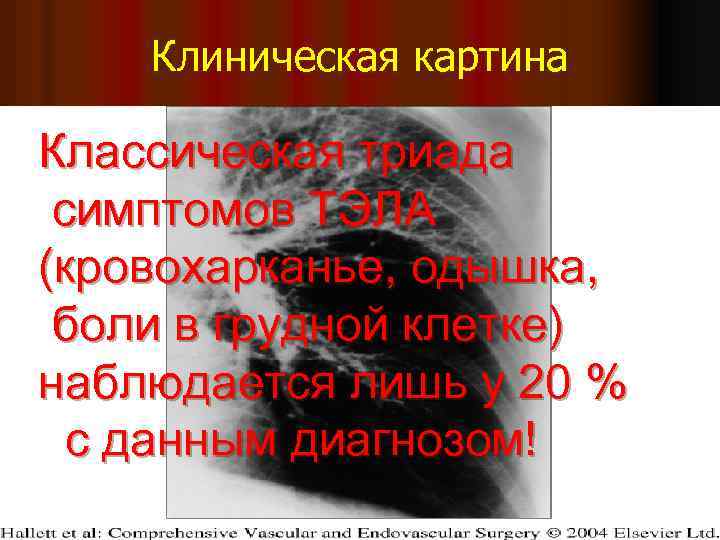

Клиническая картина Классическая триада симптомов ТЭЛА (кровохарканье, одышка, боли в грудной клетке) наблюдается лишь у 20 % с данным диагнозом!